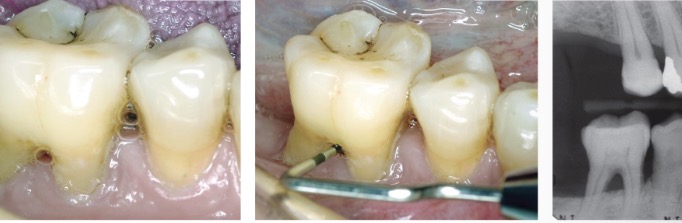

infrabony defects

classified by the number of bony walls surrounding the tooth

three-wall: three bony walls remain and one is missing

two-wall: two bony walls remain and two are missing, interdental crater most common

one-wall: one bony wall remains and three are missing, hemiseptum (only the buccal or lingual wall remains)

osseous crater

when bone loss occurs in the interdental alveolar bone, the contour of the bone from facial to lingual dips apically

affects two adjacent root surfaces to a similar extent

furcation involvement

on a multi-rooted tooth when periodontal infection invades the area between and around the roots, resulting in a loss of alveolar bone between the roots of a multirooted tooth